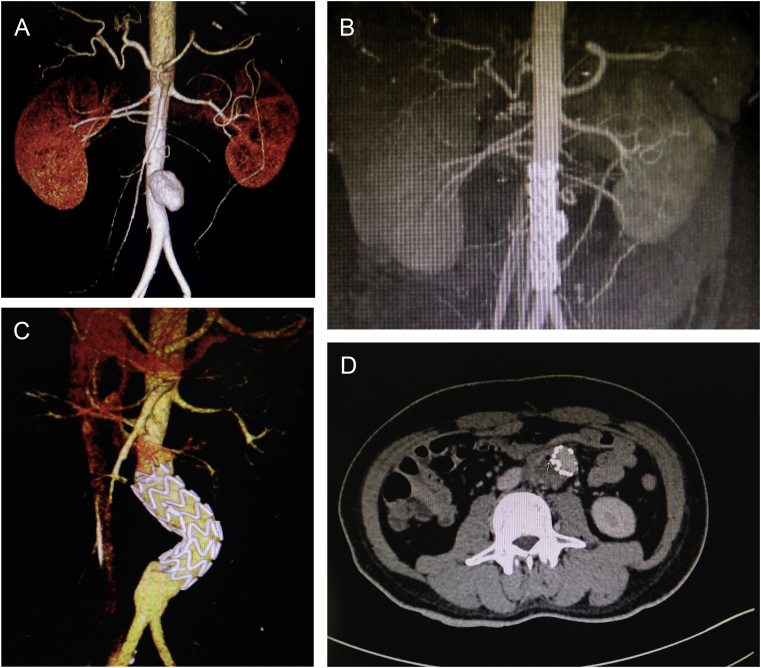

A 42 year old man with a confirmed one year diagnosis of BD was admitted with a two day history of abdominal pain. Computed tomography (CT) showed a 5 cm saccular aneurysm 5 cm below the right renal artery and 3 cm above the aortic bifurcation. The diameter of the aorta above and below the aneurysm was 16 mm and 15 mm respectively (Fig. 1A) The C-reactive protein (CRP) level was 124 mg/L. The erythrocyte sedimentation rate (ESR) was 110 mL/hour. The white blood count (WBC) was 11,000/mm3 and it was assumed that the AAA was a complication of BD. An urgent repair was performed using an off the shelf 20 mm Endurant Iliac tube limb endoprosthesis (ENEW2020C80EE) (Medtronic, Minneapolis, MN) inserted percutaneously via the right common femoral artery. The abdominal pain was resolving and the patient was discharged home 5 days later. Follow up CT scans performed three and six months after the procedure demonstrated a decrease in the size of the aneurysm sac without endoleak, migration, or kinking of the stent graft (Fig. 1B). The patient had regular follow up visits and controlled his BD with oral prednisolone (60 mg/dL) and colchicine (60 mg/dL).

(A) A computed tomography (CT) scan showing an infrarenal saccular abdominal aortic aneurysm (AAA) 5 cm in diameter, 5 cm below the right renal artery and 3 cm above the aortic bifurcation. The diameter of the aorta above and below the aneurysm is 16 and 15 mm respectively. (B) Six month post-procedure follow up CT scan demonstrating no endoleak, migration, or kinking of the stent graft. (C) CT scan demonstrating migration and kinking of the stent graft, which takes up space in the sac causing migration of the distal landing zone. The proximal landing zone and distal landing zone become aneurysmal, caused by an oversized stent graft and fragile aortic tissue. (D) A CT scan with oral contrast showing close contact and loss of the fat streak between the bowel and the aneurysm with air in the aneurysm sac.

Thirteen months after repair, the patient was admitted as an emergency with haematemesis and melaena. A CT scan showed migration and kinking of the stent without endoleak (Fig. 1C). A CT scan with oral contrast showed close contact and loss of the fat streak between the bowel, and air in aneurysm sac (Fig. 1D). The positive findings in laboratory data were as follows: leukocytosis (WBC, 12,000/mm3) with predominantly polymorphonuclear leukocytes; ESR of 40 mg/dL and CRP of 35 mg/dL. Endoscopy was performed, but the findings were unremarkable.

Urgent endovascular repair of an AAA was performed in the patient 13 months previously using the only available off the shelf Endurant iliac tube limb endoprosthesis (Medtronic, Minneapolis, MN, USA), which was 25–30% oversized. The excessive oversizing of the stent graft caused a discrepancy between the aorta above, below, and at the level of the endograft (Fig. 1C). The pathogenesis of aorto-enteric fistula after endovascular abdominal aortic repair was due to mechanical failure of the stent graft and kinking of the device in the aneurysm sac, which led to aortic graft erosion and pressure necrosis of the bowel wall.5, 6, 7 In addition, aorto-enteric fistula was precipitated by inflammatory aortitis after endovascular repair in BD (Fig. 2A).